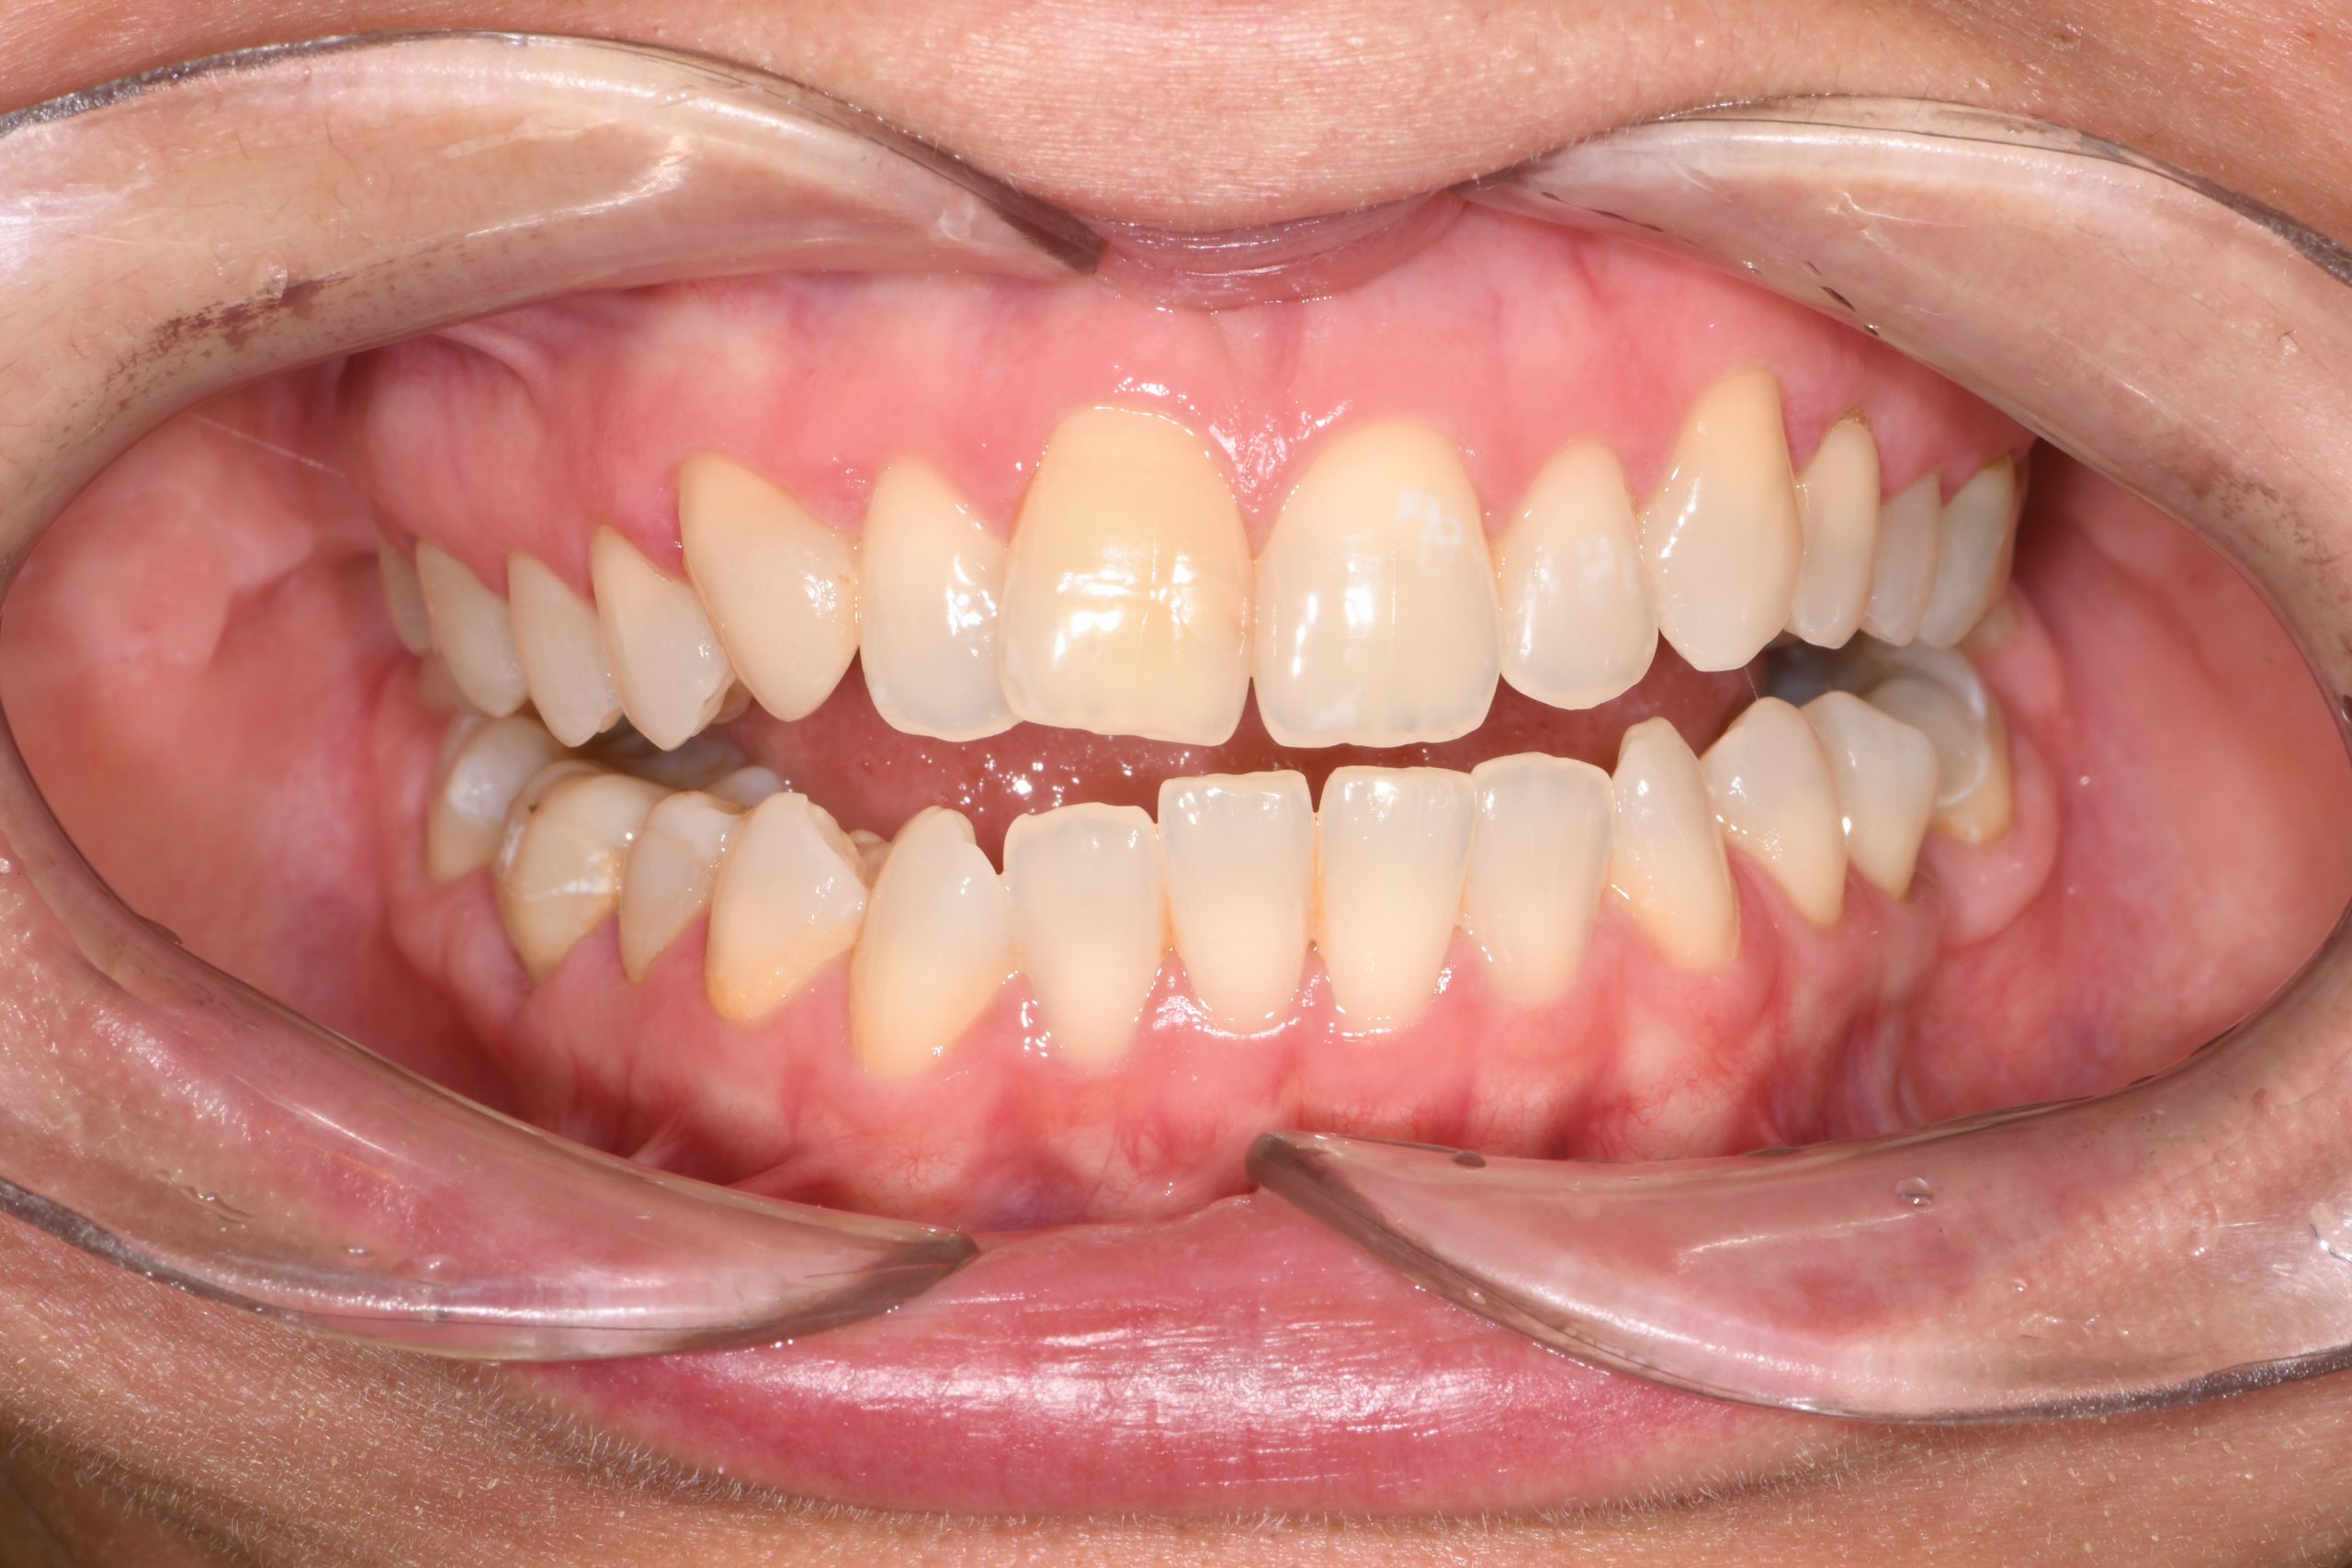

Az elmúlt évekből rengeteg szakmai referenciát tudnánk bemutatni, amelyek különböző fogszabályozási problémákat oldottak meg. Válogatva a több száz esetből, ezen az oldalon olyan képeket, információkat igyekeztünk bemutatni, amelyeknek a segítségével a jövőbeni pácienseinknek azt tudjuk üzenni: A Te fogsorod is lehet gyönyörű!

(Képeket a Pácienseink külön írásos beleegyezésével mutatjuk be!)